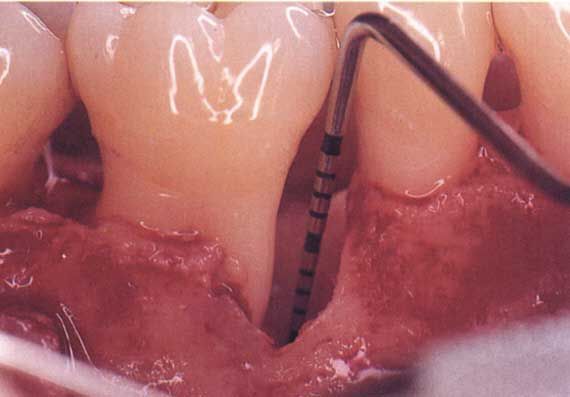

- si effettua un taglietto delle gengive e una pulizia delle radici con anestesia locale di tipo classico (curettage a cielo aperto);